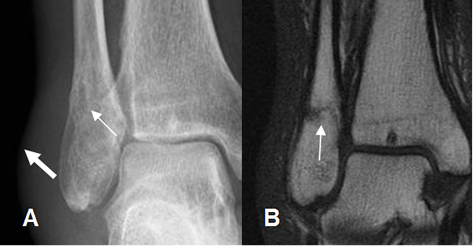

Fig 44. Fractura del maléolo externo.

A: Rx AP y B: RM corte coronal en T2. Fractura no desplazada del maléolo externo (Flecha delgada), con edema de tejidos blandos. (Flecha gruesa).